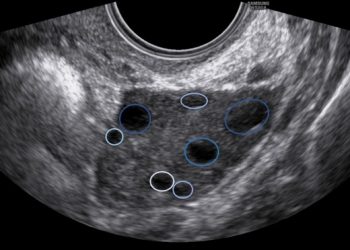

Per il mese di Gennaio SIEOG Giovani e il Comitato di Studio in Ecografia Ginecologica presentano il Webinar sulla Patologia...